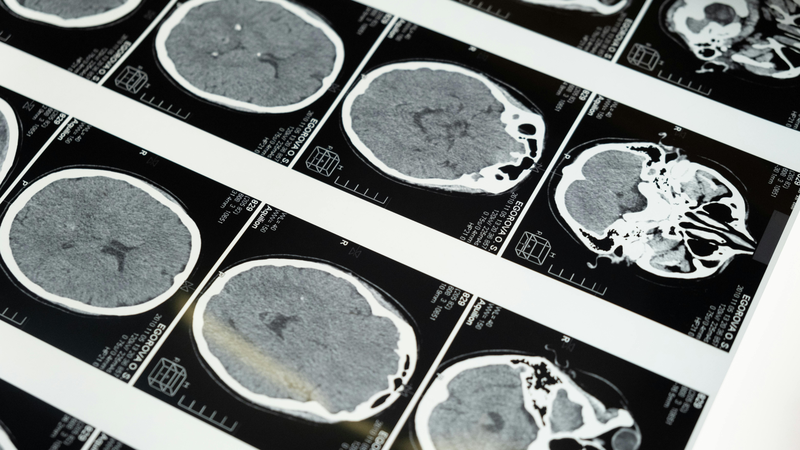

Khi hệ thần kinh trung ương bị tấn công, hậu quả thường rất nghiêm trọng và đôi khi không thể phục hồi. Trong đó, viêm màng não mủ và viêm não mô cầu là hai bệnh lý đặc biệt đáng lo ngại vì tốc độ tiến triển nhanh, triệu chứng phức tạp và nguy cơ tử vong cao. Những căn bệnh này thường không được phát hiện kịp thời do biểu hiện ban đầu dễ nhầm lẫn với cảm cúm hay sốt siêu vi thông thường.

Viêm màng não mủ là tình trạng viêm nhiễm nghiêm trọng tại các lớp màng bao quanh não và tủy sống, chủ yếu do vi khuẩn gây ra. Các tác nhân vi khuẩn thường gặp nhất bao gồm Streptococcus pneumoniae, Haemophilus influenzae type b (Hib), và một số chủng của Neisseria meningitidis. Những vi khuẩn này có thể xâm nhập vào cơ thể qua đường hô hấp, tai giữa, hoặc lan từ các ổ nhiễm trùng khác trong cơ thể.

Biểu hiện của viêm màng não mủ thường khởi phát đột ngột với sốt cao, đau đầu dữ dội, buồn nôn, nôn, sợ ánh sáng và cổ cứng. Trẻ nhỏ có thể biểu hiện bằng tình trạng bỏ bú, quấy khóc, ngủ li bì, hoặc thóp phồng. Các triệu chứng thần kinh như co giật, lú lẫn hoặc rối loạn ý thức là dấu hiệu cho thấy bệnh đã tiến triển nặng.

Dù được điều trị kịp thời, viêm màng não mủ vẫn có thể để lại nhiều di chứng nặng nề như giảm thính lực, liệt, rối loạn phát triển trí tuệ hoặc động kinh mãn tính. Tỷ lệ tử vong dao động từ 10 đến 20%, thậm chí cao hơn nếu bệnh nhân không được điều trị trong vòng 24 đến 48 giờ đầu.

Viêm não mô cầu là bệnh nhiễm trùng hiếm gặp nhưng cực kỳ nguy hiểm, do vi khuẩn Neisseria meningitidis gây ra, có thể làm viêm cả màng não và phần trong não. Vi khuẩn này thường lây qua hít phải các giọt nhỏ chứa vi khuẩn từ người mang mầm bệnh, đặc biệt dễ lây ở nơi đông người. Sau khi vào cơ thể, chúng không dừng lại ở mũi họng mà có thể đi vào máu, vượt qua rào cản sinh học và gây viêm não toàn diện.

Triệu chứng của viêm não mô cầu có thể tương tự với viêm màng não mủ nhưng thường nặng hơn và lan rộng hơn. Bệnh nhân có thể sốt cao liên tục, đau đầu dữ dội kèm buồn nôn, xuất hiện phát ban dạng xuất huyết, rối loạn ý thức, động kinh hoặc hôn mê sâu. Trong nhiều trường hợp, bệnh nhân nhanh chóng rơi vào tình trạng sốc, tụt huyết áp, rối loạn đông máu và suy đa cơ quan.

So với viêm màng não mủ, viêm não mô cầu có tỷ lệ tử vong cao hơn rõ rệt, có thể lên đến 30% nếu không được phát hiện và điều trị kịp thời. Dù được cứu sống, nhiều bệnh nhân vẫn sống chung với các di chứng nặng nề như mất thính lực, liệt nửa người, suy giảm trí nhớ hoặc thay đổi hành vi kéo dài.